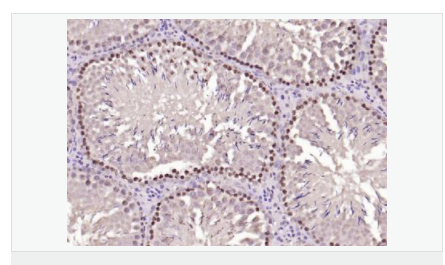

交叉反應(yīng):Human,Mouse,Rat(predicted:Dog,Pig,Rabbit,GuineaPig) 推薦應(yīng)用:IHC-P,IHC-F,ICC,IF,Flow-Cyt,ELISA

| 產(chǎn)品應(yīng)用 | ELISA=1:5000-10000 IHC-P=1:100-500 IHC-F=1:100-500 Flow-Cyt=1μg/Test ICC=1:100 IF=1:100-500 (石蠟切片需做抗原修復(fù)) not yet tested in other applications. optimal dilutions/concentrations should be determined by the end user. |